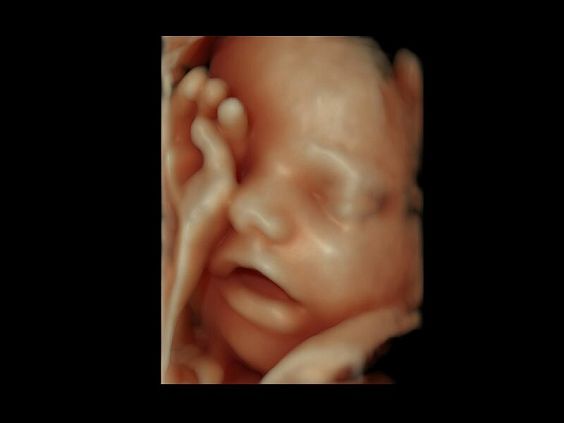

• Автоматическое определение плода в режиме 3D (SonoRenderLive) – позволяет значительно экономить время и получать изображение конечностей и лица плода в режимах 3D без артефактов и помех – система автоматически определяет границы конечностей и лица плода и выстраивает объемное изображение

Современные клинические приложения и высокое качество изображений позволяют использовать Voluson E10 для наблюдения за ходом беременности максимально эффективно. С помощью этого аппарата можно проводить любые исследования, как рутинные, так и комплексные, выявляя проблемы на ранних стадиях и принимая своевременные меры.

Объемное сканирование Voluson — 3D/4D вашей мечты

Объемное УЗИ на Voluson E10 — это не просто потрясающе красивая картинка, это ценный инструмент получения дополнительной информации при обследовании женщин.

Voluson E10 поддерживает инновационные технологии формирования изображений — HDlive Silhouette и HDlive Flow, которые позволяют увидеть мельчайшие детали. Алгоритм SonoRenderlive упрощает рабочий процесс и дает возможность реконструировать изображение поверхностей, определяя область перехода между тканью и жидкостью.

• SonoRenderlive

• Улучшает объемную визуализацию за счет автоматического определения линии начала реконструкции при изображении поверхностей. При исследовании в режиме 4D функция SonoRenderlive непрерывно обновляет положение исходной линии с учетом движений плода.